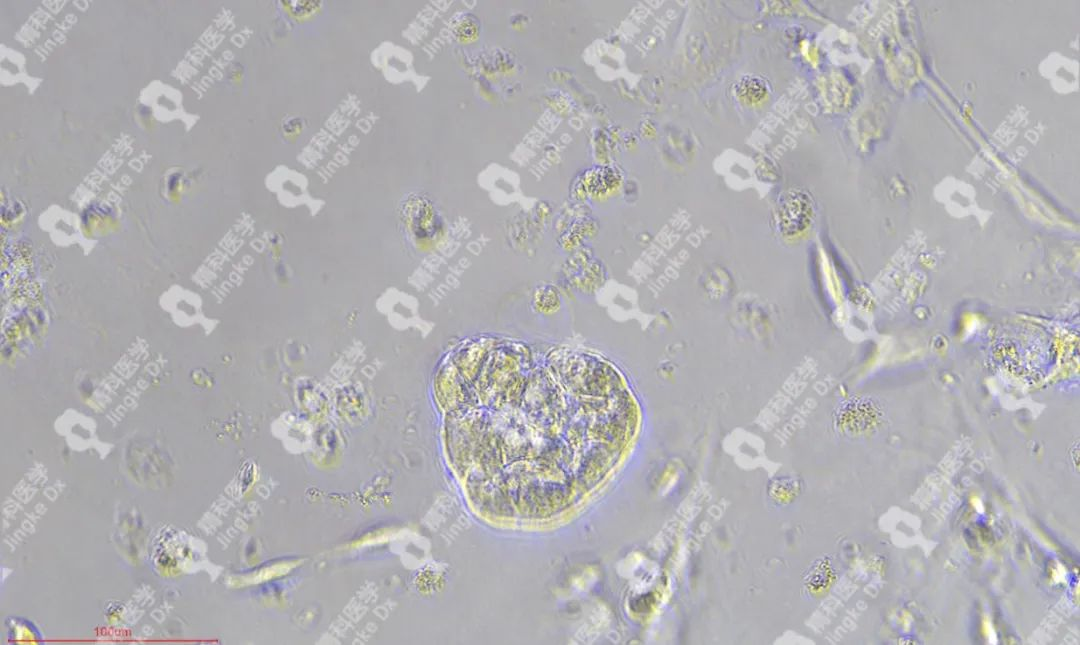

PIC.01

精科卵巢癌類(lèi)器官圖像